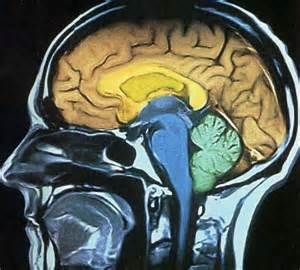

人腦構造據國外媒體報導,目前科學家發現人類大腦中的“開關裝置”,能夠幫助昏迷患者恢復意識。

一位54歲患者大腦屏狀核(大腦中心下方一個較薄的神經組織)受到高頻刺激時,研究人員發現患者失去知覺處於昏迷狀態。這意味著她無法回響外界指令、兩眼發直和呼吸減慢,一旦對屏狀核的高頻刺激停止,這位患者將恢復知覺,同時對於剛才發生的一切全然不知。

在接下來的兩天,研究人員每次對患者屏狀核進行刺激實驗,出現的情況都是一樣的,同時,研究證實這並非是癲癇症的副作用。考貝西將這種效果比作汽車點火裝置,它將啟動汽車其它部件。

當患者處於昏迷低意識狀態,刺激大腦屏狀核將有助於恢復知覺。科學家下一步將在其它患者進行實驗,進而確定屏狀核對於意識知覺的真實作用。